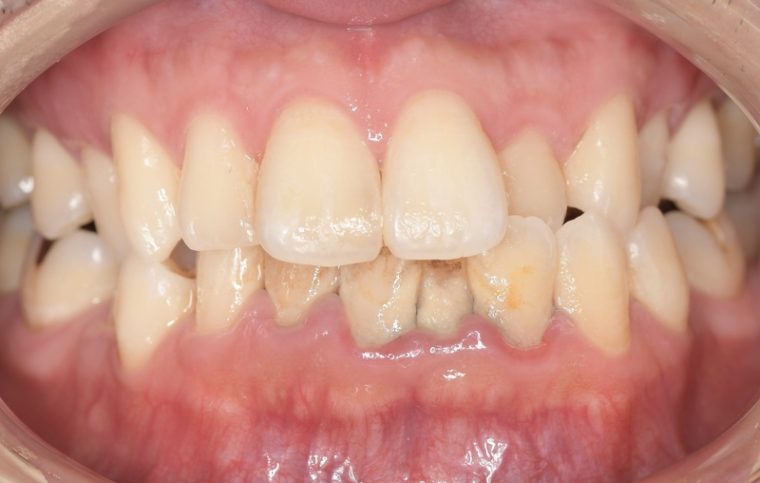

クリーニングの症例

現在の治療費と異なる場合がございます。最新の治療費は料金表をご確認ください。CASE 1

Before

After

基本情報

| 主訴 | 見た目をきれいにしたい |

| 治療期間 | 6ヶ月 |

| 治療費 | ジルコニアボンド(セラミックの被せもの)¥165,000×7(税込み) オフィスホワイトニング4回 ¥4,400×4(税込み) ホームホワイトニング¥11,000 |

| リスク・副作用 | かみ合わせがとても強い方の場合、稀に割れてしまうことがあります。 |

| 先生からの提案 | 上の前歯6本と右下の2番目の歯はセラミックの被せもので治療。 残りの下の前歯5本はプラスチックの材料で虫歯を治療し、 ホワイトニングをおこないました。白くなったご自身の歯の色に合わせてセラミックの 被せものを作成しています。 模型上で完成後をシュミレーションし、上の歯茎の位置をきれいに見えるように 揃えています。(外科処置はしていません) |